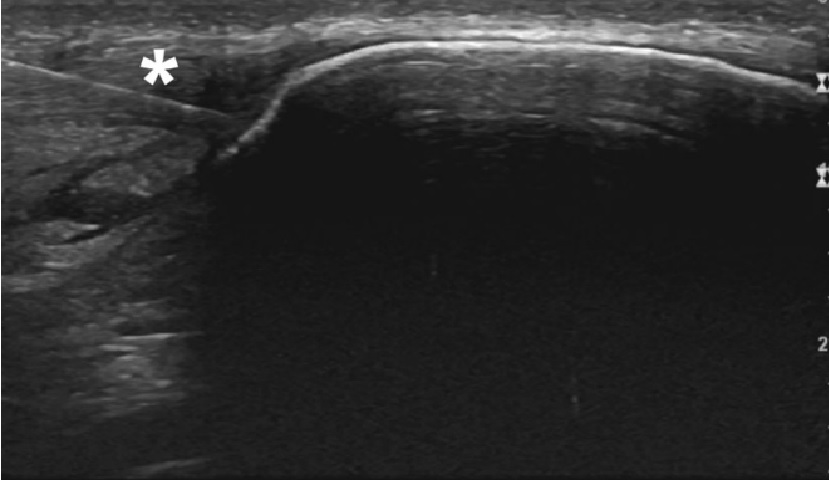

Ultraljudsvägledd Epte - Electrolysis percutaneous therapy

Epte är en mycket bra och specifik behandlingsmetod för behandling av tendinopatier, alltså problem i från senor och muskler efter överbelastningar. De problem som kan behandlas med Epte är hopparknä (smärta vid knäskålen), tennisarmbåge, golfarmbåge supraspinatussena och infraspinatussena i axeln, hälsena, hälsporre (plantar fasciit). Epte används på både idrottsaktiva och mindre aktiva.

Med hjälp av den lokala strömmen framkallas en lokal kontrollerad inflammation för att få till en läkning. Inflammation är den process man vill ha efter en överbelastning då det är den process som läker skadan. Vid problem i senor (tendinopatier) är det ofta är avsaknaden av inflammatorisk process eller en för liten inflammation som gör att det ofta inte läker som det ska och istället blir till en degenerativ process i senan.